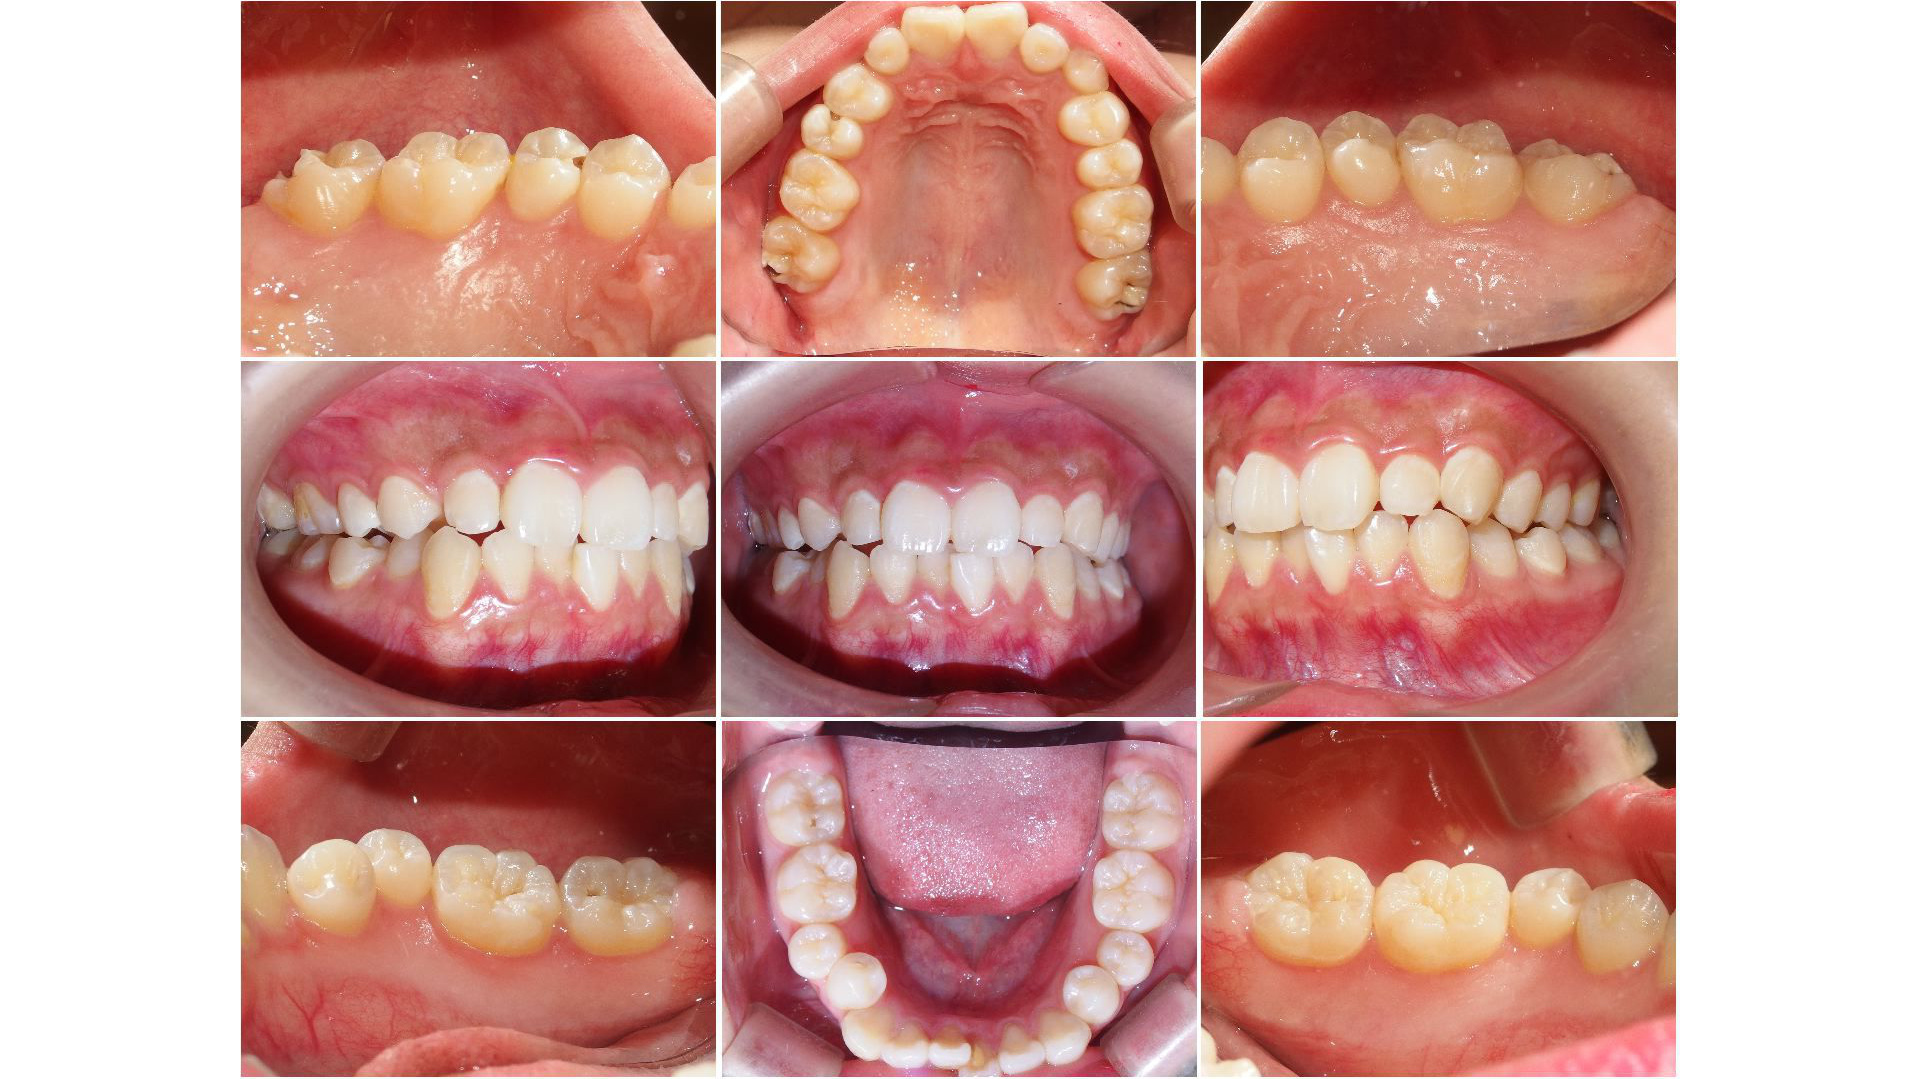

④ お口の中の写真撮影

患者さんの現在の状態をご説明するために、一眼レフカメラを用いてお口の中の写真を撮影いたします。撮影した写真を使うことによって、より治療がイメージしやすくなります。また、この写真はずっと保存していきますので、将来的な変化があった場合にも比較ができます。